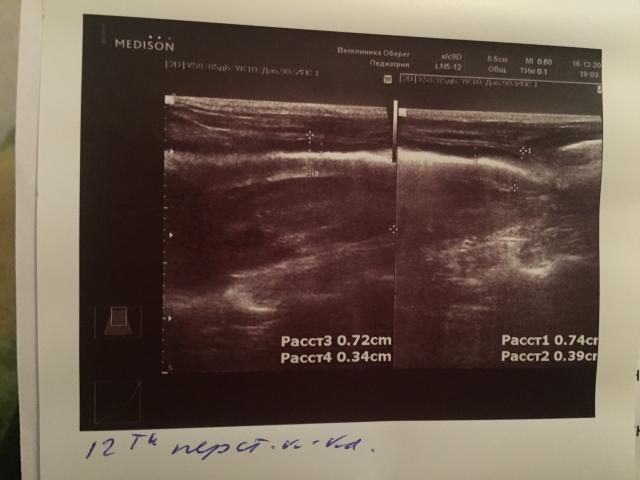

Если можно, то немного подробнее. На основании чего вам поставили такой диагноз, только на основании проведенного УЗИ? Может быть, собаке брали какие-то анализы? Если да, то выложите, пожалуйста, здесь их результаты. Если только данные УЗИ, то это разговор ни о чем (я имею ввиду панкреатит). Гастрит по данным УЗИ вообще не ставят.

К сожалению, ничего не могу рассмотреть. Попробуйте сами прочесть описание с фото. Если сможете, сделайте снимок более качественным. Или можно снять крупнее по частям. Может быть, тогда буквы будут видны более четко.

Спасибо, фотографии четкие. Я все прочитал. Как я и думал, там и "не пахнет" никаким гастродуоденитом, а тем более, панкреатитом.